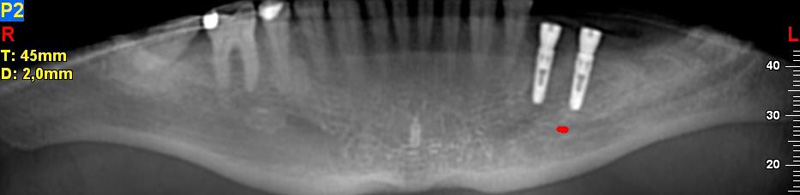

NewTom Implant Planning na plánování vhodných pozic pro zavedení implantátů. Dalším plánovacím softwarem, který umožňuje i zhotovení operačních šablon pro přesné zavádění implantátů - tzv. navigovaná implantologie, je software

NewTom Implant Planing

Jedná se o plánovací program, který využívá dat získaných při vyšetření pomocí přístroje New Tom. Tento program umožňuje tříprostorovou počítačovou simulaci při plánování pozic implantátů.

Součástí programu je i databáze, ve které mohou být uloženy všechny typy implantátů od všech výrobců, včetně jejich délek, průměrů i tvarů.

Lékař si vytvoří všechny typy zobrazení potřebných pro naplánování – tedy 2D snímky (panoramatický), příčné řezy i 3D model.

Vidí zde i důležité anatomické útvary – čelistní dutinu, průběh nervu atd. Po proměření množství kosti – šířky i výšky vybere z databáze vhodný typ implantátu a umístí ho do požadované lokality.

Ihned vidí jeho pozici ve všech 3 rovinách a na všech snímcích i 3D modelu. Může upravovat podle potřeby jeho pozici, sklon atd.

Všechny vybrané a správně umístěné simulované implantáty se ukládají do „počítačové karty“ pacienta s jejich pozicí, délkou, průměrem, typem i sklonem.

Lékař i pacient tedy ještě před vlastní operací vidí, jak by mělo ošetření probíhat a vypadat.